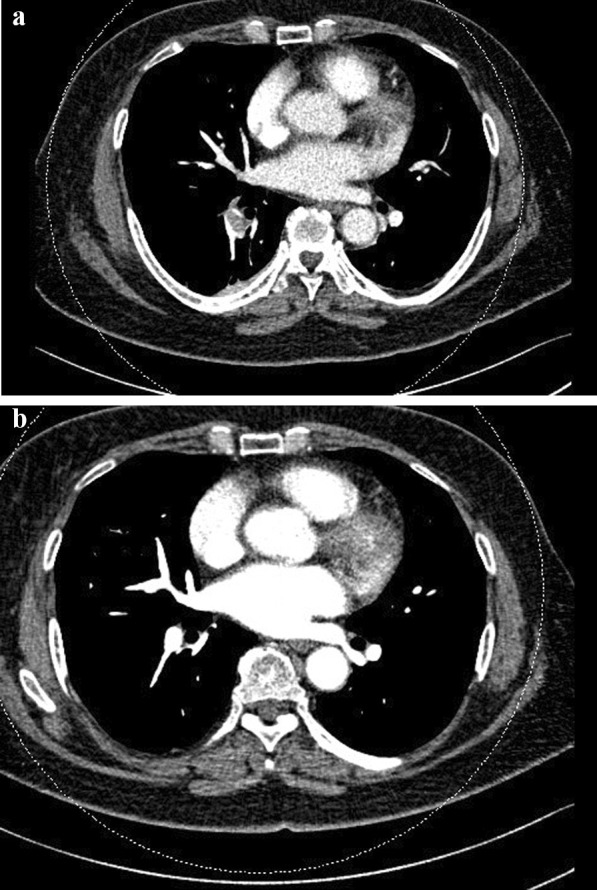

Materials and methods: We consecutively examined 1645 patients who underwent TKA between January 2015 and November 2019. Postoperative SpO2 was measured with a pulse oximeter, which was stopped if SpO2 was maintained at ≥ 95% until postoperative day 2 (POD2). To diagnose PE, computed tomographic pulmonary angiography (CTPA) was performed for specific indications, including persistently low SpO2 < 95% (group 1), sudden decrease in SpO2 (group 2), and decrease in SpO2 after POD3 with presenting symptoms (group 3). Also, we divided the patients into unilateral, simultaneous and sequential TKA groups and compared the results with specific statistical techniques.

Results: Of the 1645 patients who underwent TKA, there were 20 patients with PE (1.2%), and symptomatic PE was observed in only 4 patients (0.24%). CTPA was performed in 58 (3.5%) patients, of whom 20 were diagnosed with PE. In groups 1 (n = 34), 2 (n = 21), and 3 (n = 3), CTPA was performed 2.4, 2.6, and 8.3 days after TKA, respectively, and 12, 8, and 0 patients were diagnosed with PE, respectively. Of the 782, 416, and 447 unilateral, simultaneous, and sequential (done in same admission with interval 1 or 2 weeks) patients with TKA, 38, 18, and 2 received CTPA, and 13, 6, and 1 were diagnosed with PE, respectively. All patients diagnosed with PE have persistently low SpO2 < 95% (group 1), or sudden decrease in SpO2 (group 2) until POD2. Of the patients diagnosed with PE, SpO2 decreased without the presentation of symptoms in 16 patients (11 and 5 from groups 1 and 2, respectively) and with the presentation of symptoms, such as mild dyspnea and chest discomfort, in 4 patients (1 and 3 from groups 1 and 2, respectively).

Conclusions: Measuring SpO2 using a pulse oximeter until POD2 was an effective method for early diagnosis of PE after TKA. No case of morbidity or mortality was observed after early diagnosis with early stage CTPA and management of PE. We recommend measuring SpO2 with a pulse oximeter for early diagnosing of PE in TKA.